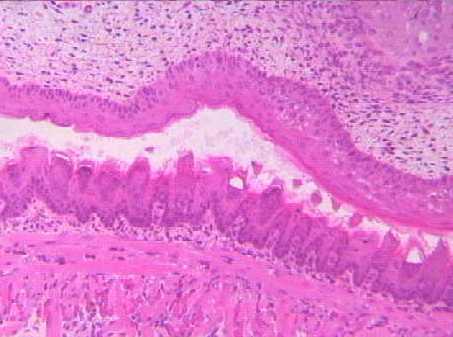

切片位置:口腔 (oral cavity)

切片倍率:100x

染色方式:h&e stain

低倍下(100x)之口腔切片,可見上顎及舌頭之上皮組織均由角質化複層鱗狀上皮所組成。